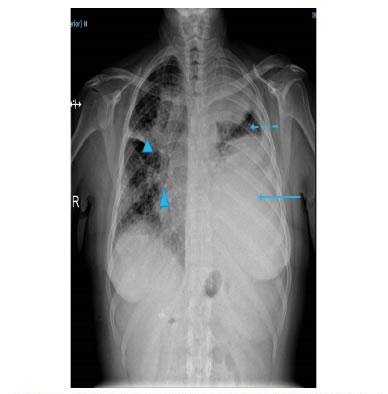

Se trata de una mujer de 39 años con un tumor ulcerado dependiente de la mama izquierda. El reporte remitido de la histopatología de la biopsia por incisión, informó adenocarcinoma de mama.

Al ingreso presentaba disnea, ingurgitación yugular a 30 grados, pulso paradójico, taquicardia, frote pericárdico y ausencia del murmullo vesicular en el hemitórax izquierdo.

En la radiografía de tórax se observó derrame pleural izquierdo y aumento del tamaño de la silueta cardiomediastínica (figura 9).En la TC de tórax se apreciaba derrame pericárdico, con tabiques, derrame pleural izquierdo, y engrosamiento pleural y pericárdico (figura 10).

Se le practicó una ventana pericárdica izquierda mediante toracotomía asistida por video (VATS) y se le instaló un catéter subcutáneo (tunnelized) pleuro-pericárdico temporal (figura 11).

En el estudio citológico y del bloque celular del líquido pericárdico, se reportó neoplasia maligna: carcinoma. En la histopatología del pericardio se informó adenocarcinoma de mama. En la inmunohistoquímica, los receptores de estrógeno y de progesterona, la proteína GATA y la mamoglobina, fueron positivos, y el protooncogén HER2/neu, negativo (figura 12).